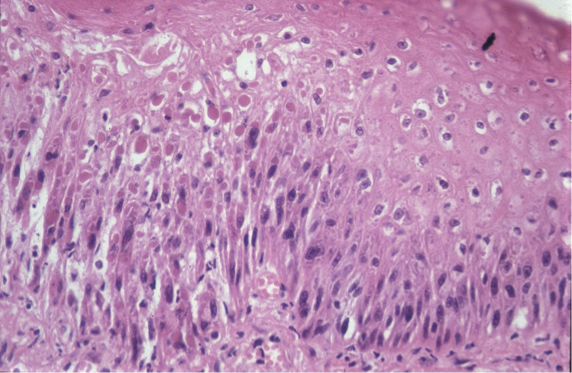

How does orf present histologically?

Spongiosis

Micropustules

Epidermal hyperplasia

Intra-cytoplasmic inclusion bodies